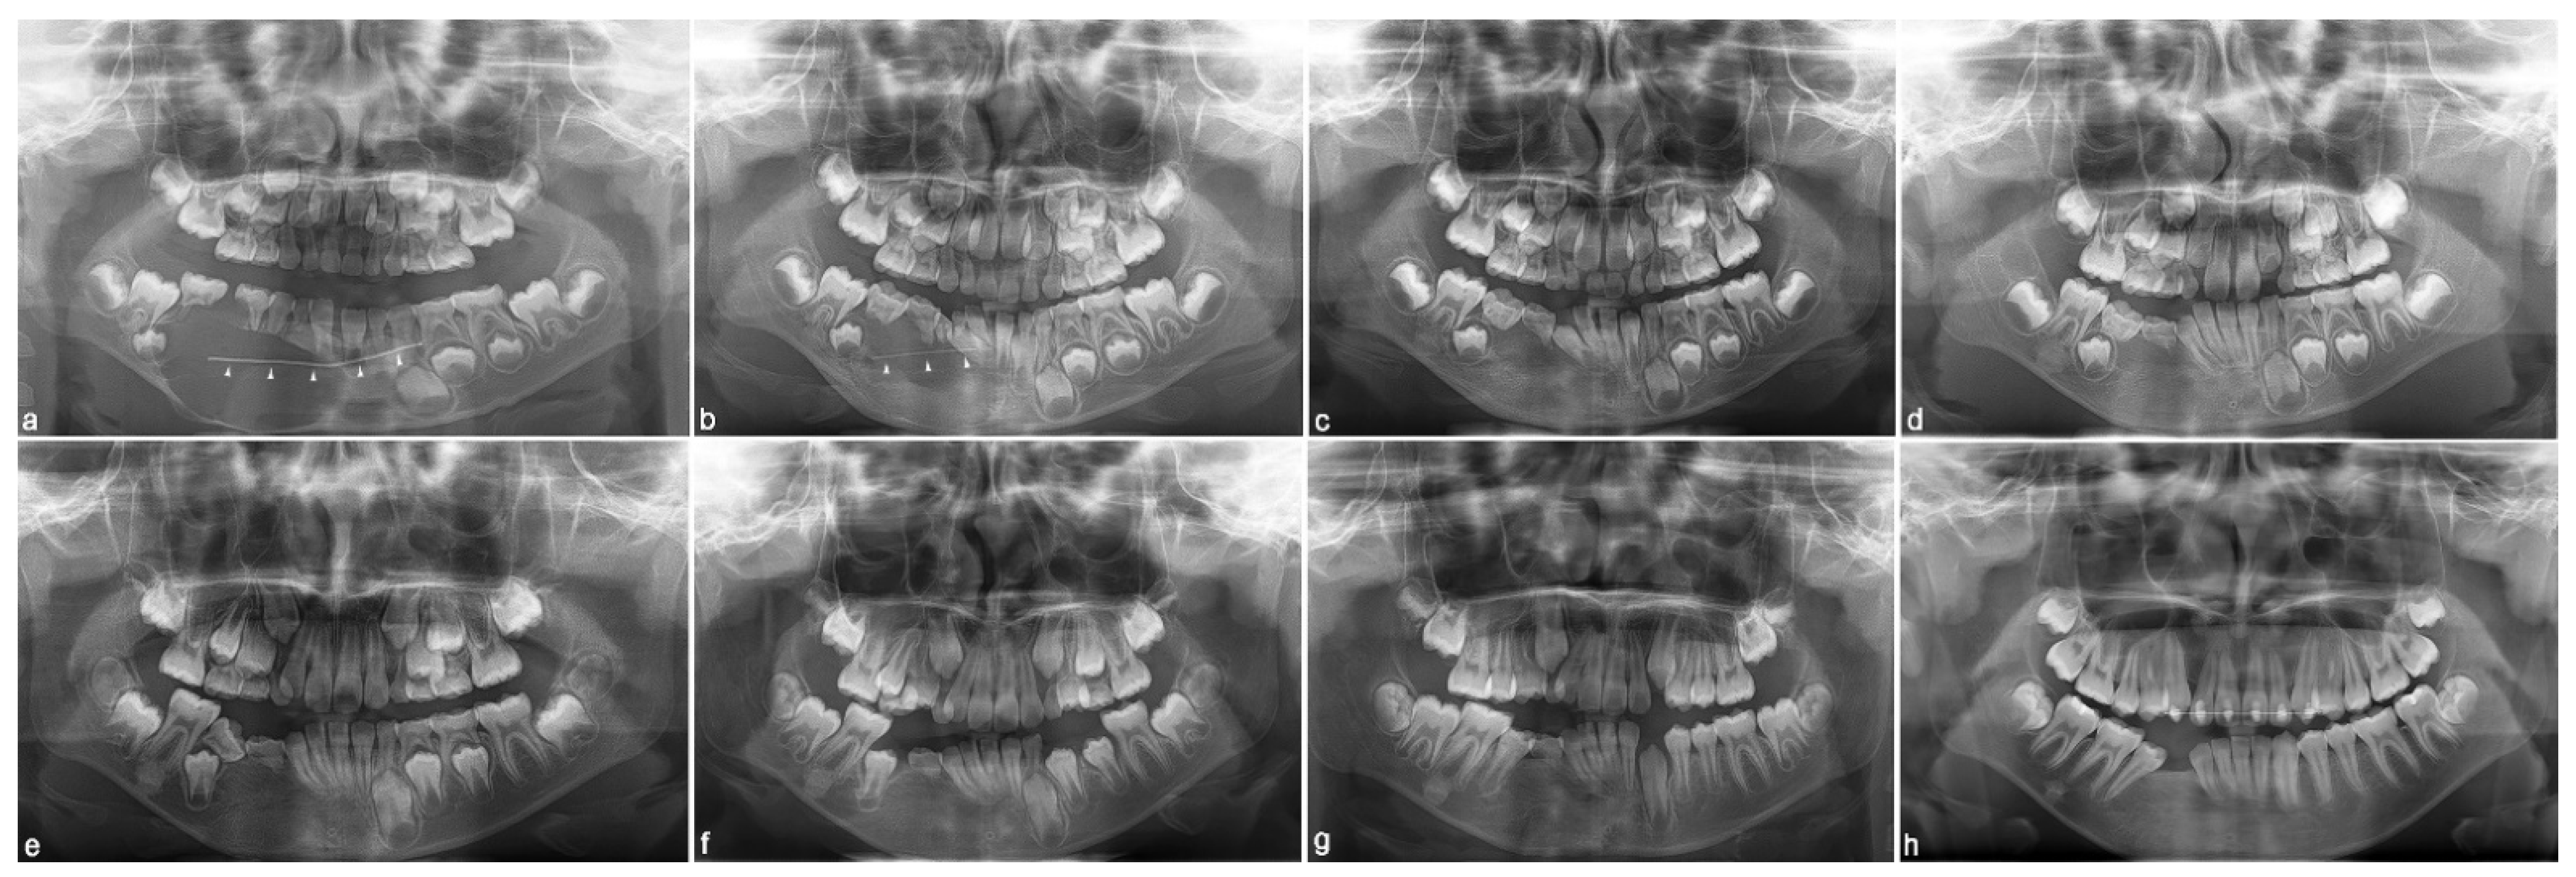

2. Case Report